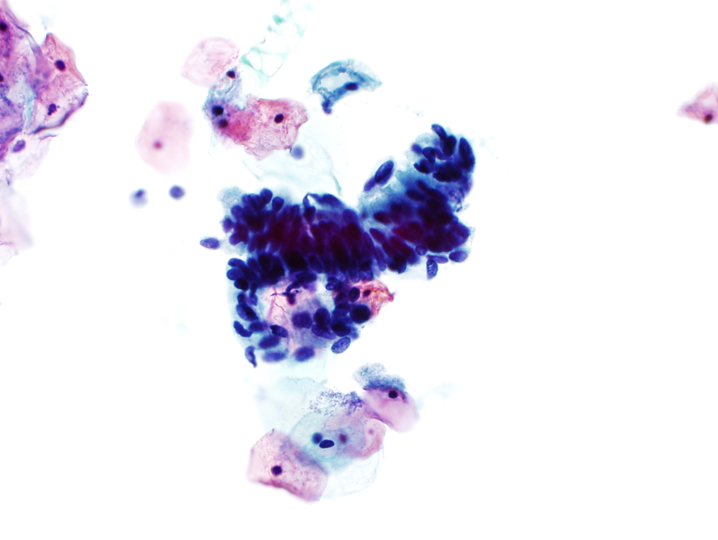

- Atypical endocervical cells, favor neoplastic

- Abnormal cells occur in sheets and strips with nuclear crowding, overlap or pseudostratification

- Rare cell groups with rosettes (gland formations) or feathering

- Nuclei are enlarged and often elongated with some hyperchromasia and coarse chromatin with heterogeneity

- Occasional mitoses or apoptotic debris

- Cell borders may be ill defined

Cytology images

A. Atypical glandular cells, favor neoplastic. The image shows endocervical cells with crowding, nuclear overlap, hyperchromasia and focal feathering. Answers B, C and D are incorrect because cytologic features of endometrial adenocarcinoma, HSIL and tubal metaplasia are not seen.